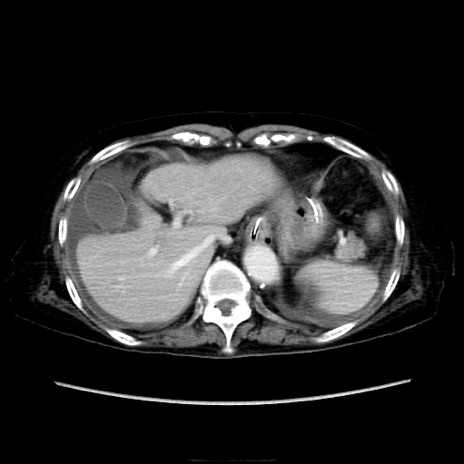

症例40(横断像)

【症例】90歳代女性

【主訴】腹痛・嘔吐

【現病歴】 食欲低下、嘔吐があり昨日他院受診。肺炎と診断され入院となる。入院後より腹部全体に圧痛あり。胃管留置され経過みていたが、症状持続するため、

当院転院となる。

【既往歴】胸椎圧迫骨折、胆石症

【身体所見】腹部:中央に激痛あり、圧痛あり、反跳痛不明

【データ】WBC 17100、CRP 18.82

横断像